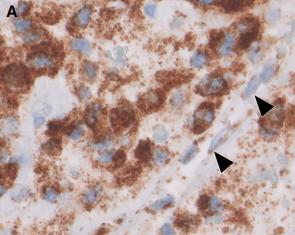

- SDHB标记: SDHA/B/C/D/AF2基因(统称SDHx)的突变或甲基化均可导致SDHB蛋白表达异常(缺失或减弱)。SDHB表达异常提示可能存在SDH缺陷相关的遗传性肿瘤综合征。本例患者SDHB蛋白表达正常。

SDHB免疫组化结果判读示例:A图为正常表达(胞浆颗粒状强阳性),B-F图均为不同模式的表达异常 [引自PMID:35546442]